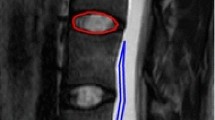

For each MC, ADC was measured in the MC related area that was most intense on the ADC map, in normal vertebral body marrow, and in cerebrospinal fluid (CSF) using a circular region of interest (ROI) with predefined size (Fig. 1, Table 2). To limit variation in ADC measurements, we did not use freely shaped ROIs. If the MC area had uniform intensity on the ADC map, ADC was measured in the area where the MC had largest height on T1/T2.

Measurements of ADC values. (a-d) A 50-year-old woman with chronic low back pain. ADC maps (a, c) and corresponding T2 weighted fast spin echo images (b, d) showing MCs at the L4/L5 level. ADC measurements (Avg GY corresponding to mean 10−6 mm2/s) included (a) highest mean ADC value in the MC region (1655 in a 41.8 mm2 ROI) and (c) mean ADC in normal vertebral body marrow (215.9 in a 94 mm2 ROI) and in CSF (3125 in a 41.8 mm2 ROI). Midsagittal images were used for measurements in CSF at the level of the MC and close to the endplate in normal vertebral body marrow near the MC. ADC, apparent diffusion coefficient. MC, Modic change. ROI, region of interest. CSF, cerebrospinal fluid

The ADC maps showed some noise and distortion (Fig. 1), which are common problems in spine DWI [40]. The single-shot echo-planar imaging method applied is prone to susceptibility artefacts, which can influence ADC values. The DWI sequence (3 min 48 s) was part of an extensive MRI protocol where each sequence had been shortened to reduce total scan time and make the protocol feasible at all study centres. Longer acquisition time could have been used to improve the ADC maps [45, 46]. New DWI methods like RESOLVE (readout segmentation of long variable echo-trains), can also provide better image quality but were not available to us at the time [47]. The DWI method we used should be possible to apply at most MRI centres. Importantly, we used T1/T2 images as anatomical references when measuring ADC, and the modest quality of the ADC maps hardly affected the overall results.